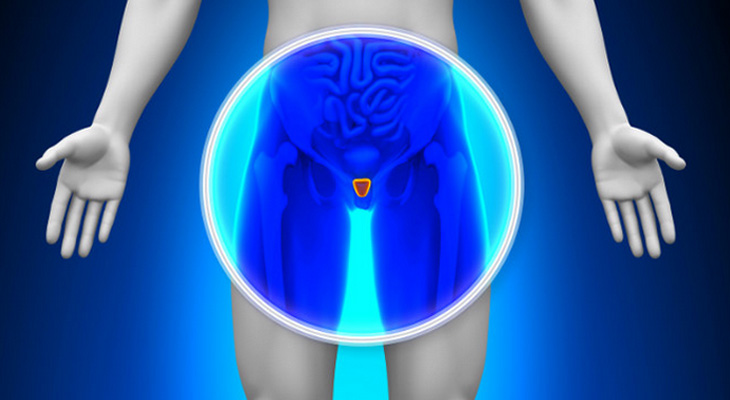

Nesta terça-feira (04), Paulinha Almeida conversou no Programa Olinda Todo dia sobre o novembro azul, tema importante para a população, especialmente para os homens. Como se prevenir ao câncer de próstata? Qual exame deve fazer para descobrir a doença? Quais os primeiros sintomas do câncer? Qual é o tratamento ideal?

Para responder essas e outras perguntas, ela conversou com a Dra. Yuki Konishi que é Urologista e especialista no assunto. Ela abordou as principais perguntas sobre esse tema e a doutora explicou melhor sobre o assunto.

“A maioria dos homens tem receio para fazer exames, pois, tem medo dos resultados, mas é superimportante fazê-los para caso obtenha a doença fazer o tratamento corretamente”.